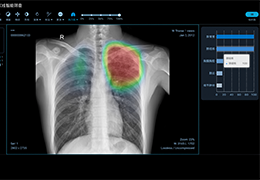

成像智能。

Eclipse 成像智能功能提供强大的处理能力和最佳质量的影像,同时减少质量错误并提高剂量效率。

凭借 AI、专有算法和先进的影像处理能力,提供出色的影像质量和无与伦比的诊断信心。

与标准影像处理相比,智能降噪功能可使客户降低辐射剂量,而不会损失影像质量。这在新生儿和儿科成像中尤其重要,在这种情况下以尽可能低的剂量成像至关重要。

提供相配视图选项,以减少所需的曝光次数,并提供更清晰的感兴趣区域视图。